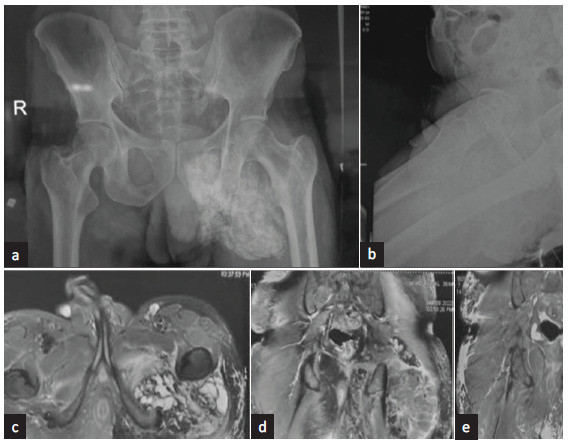

Tumoral calcinosis is a rare syndrome characterized by calcium salt deposition in different periarticular soft tissue regions. We report this case of tumoral calcinosis with history of persistent soft tissue calcifications for over three decades. He presented with nephrotic syndrome and kidney biopsy revealed secondary amyloidosis. Genetic evaluation revealed GALNT3 mutation and diagnosis of hyperphosphatemic familial tumoral calcinosis was made. With this case report, we want to reiterate the need to consider tumoral calcinosis in secondary amyloidosis differentials and the pivotal role of genetic workup in chronic soft tissue calcifications.